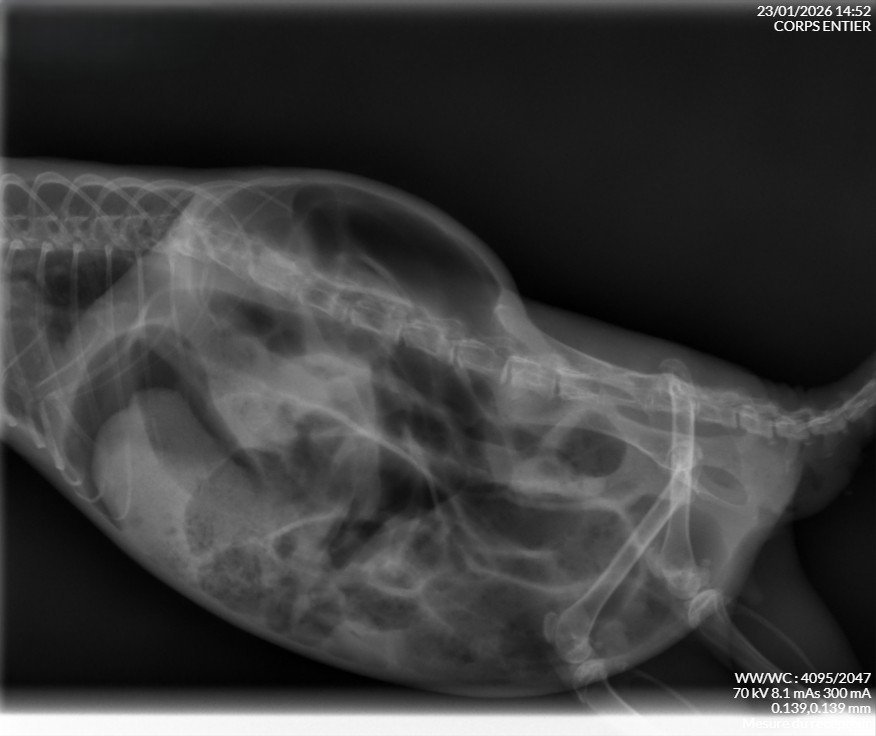

De retour de la consultation pour ma petite Suzette, dont l'état ne s'est pas dégradé cette semaine.

J'appréhendais ce rendez-vous... Au final, pas de surprise, on est bien face à un mégacôlon idiopathique.

La radio, que j'ai récupéré pour vous, n'a pas révélé d'occlusion intestinale ou de masse.

Ma petite puce reste bien vive, elle va donc rester avec nous jusqu'au jour où cela deviendra trop douloureux pour elle...

Mais aujourd'hui, on n'y est pas:panique: